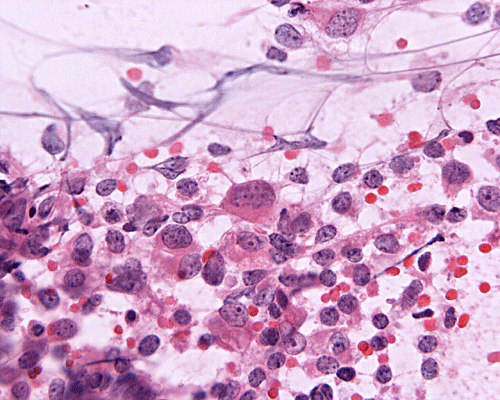

The patient was admitted to our hospital because of a large cerebellar mass that was diagnosed in an outside institution. A surgery was performed. The followings are the representative photos of this mass.

A. Squash |

Panel A was a cytologic preparation (squash preparation) and Panel B was the frozen section obtained on intraoperative consultation respectively. Panel C, D, and E were permanent sections obtained from representative areas. Panel F, G and H were cerebellar tissue that was included in the specimen.